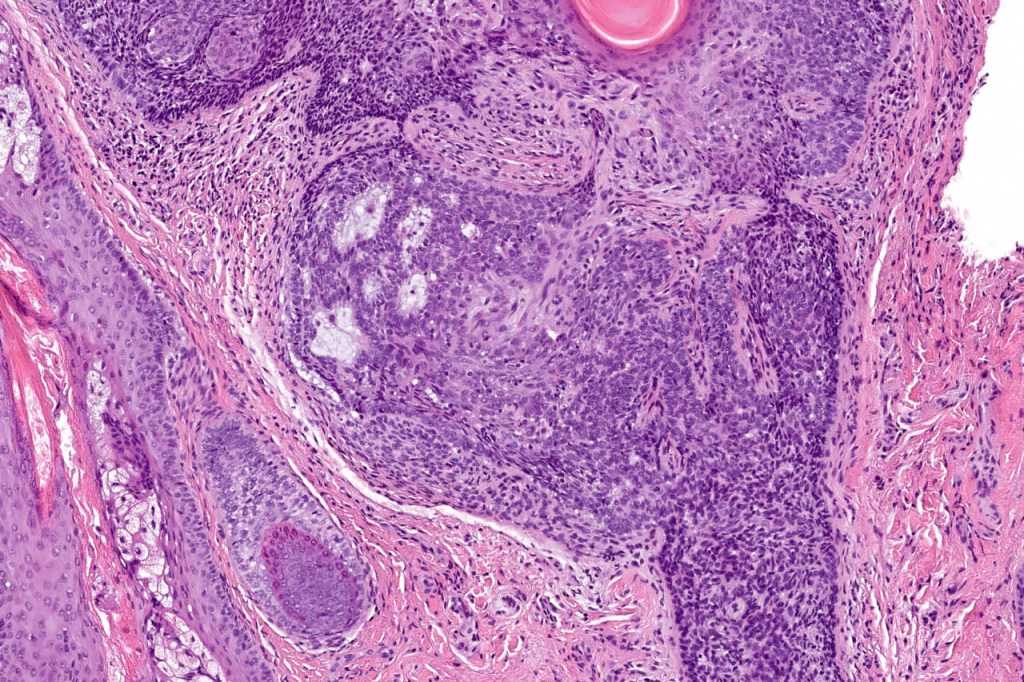

•The classical appearance consists of keratocysts & lobules of basaloid cells

•Basaloid lobules show peripheral palisading

•Retraction artifact and mucin deposition as seen in BCC are not present

•Mitoses & apoptosis may be present

•Perifollicular mesenchyme is always conspicuous and sometimes densely aggregated are seen indenting the baslaloid lobules (papillary mesenchymal bodies)

•Narrow epithelial strands arising from the basaloid lobules are often present

Trichoepithelioma should be distinguished from trichoblastoma since the latter is very rarely syndromic. Trichoepithelioma is largely a dermal tumor whereas trichoblastoma often extends from the dermis into subcutaneous fat or deeper in very large examples. Papillary mesenchymal bodies are much better formed and generally more obvious in trichoepithelioma. Trichoepithelioma must also be distinguished from basal cell carcinoma. Retraction artifact & stromal mucin are features of basal cell carcinoma and not trichoepithelioma. Papillary mesenchymal bodies are not seen in basal cell carcinoma.